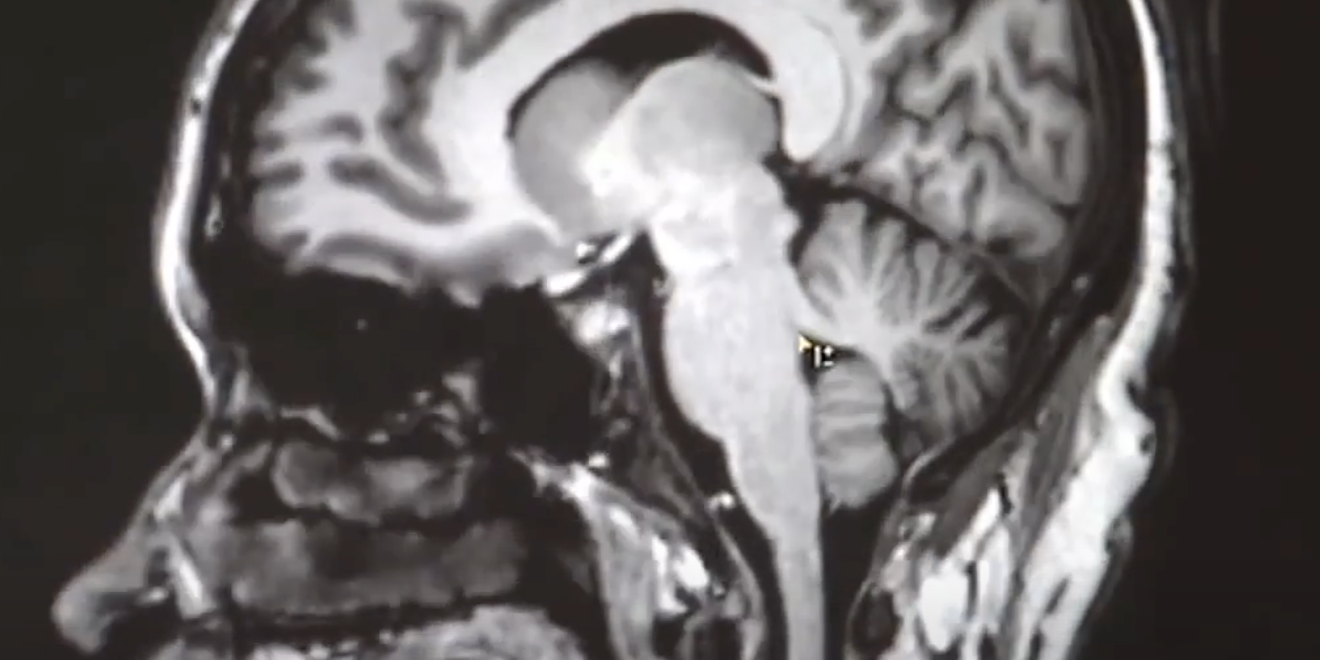

The faculty are actively engaged in basic, translational and clinical research in various neurological diseases including amyotrophic lateral sclerosis, Alzheimer’s disease, frontotemporal dementia, gene therapy in neurodegenerative disease, multiple sclerosis, ischemic hemorrhagic stroke and traumatic brain injury among others